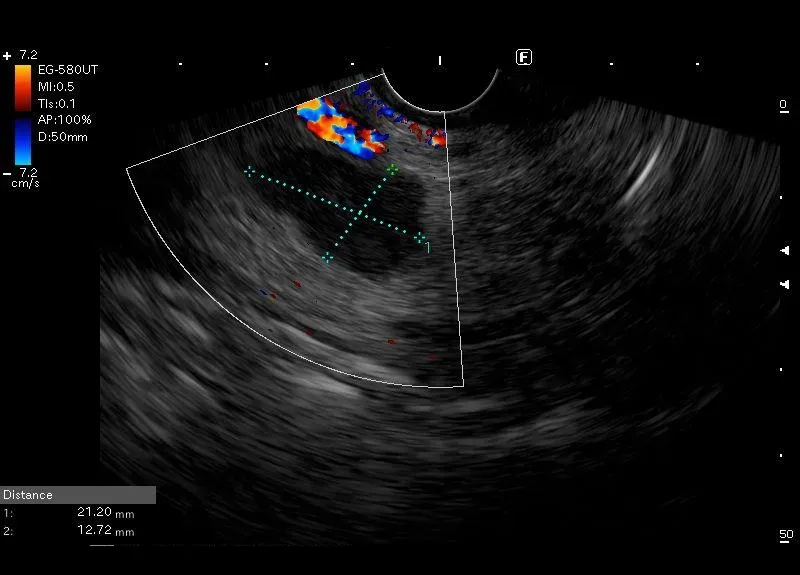

Zwykle drobne do 10 mm, owalne, nerkowate lub okrągłe, dobrze odgraniczone hypoechogerniczne zmiany, z widoczną drobną wnęką, położone w typowych miejscach, czasami jak w pokazanym przypadku powiększone.

Obraz odpowiada powiększonym węzłom chłonnym okolicy głowy trzustki.